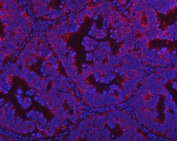

Immunofluorescent staining of FFPE human intestinal cancer with PGP antibody (red) and DAPI nuclear stain (blue). HIER: steam section in pH8 EDTA buffer for 20 min.